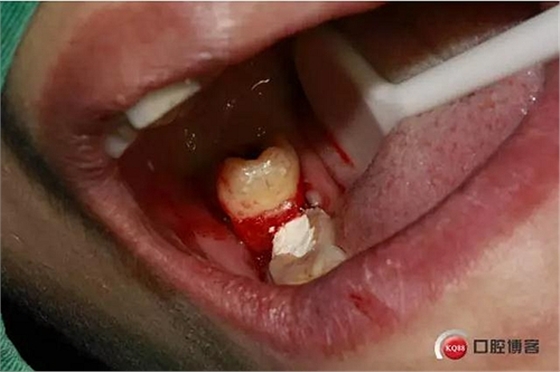

檢查:48號牙稍偏近中生長,周圍牙齦稍白,遠中齦袋中有少許滲出物,探診;未出血,叩(--),冷熱(--)。47遠 中未見齲壞,47冷熱(--)叩(--)。舌側(cè)少許齦上結(jié)石。X線檢查,48遠中有陰影約2mm,根尖在神經(jīng)管內(nèi)約2--3mm。根尖未見陰影。

口內(nèi)照片,48遠中三分之一覆蓋部分牙齦。